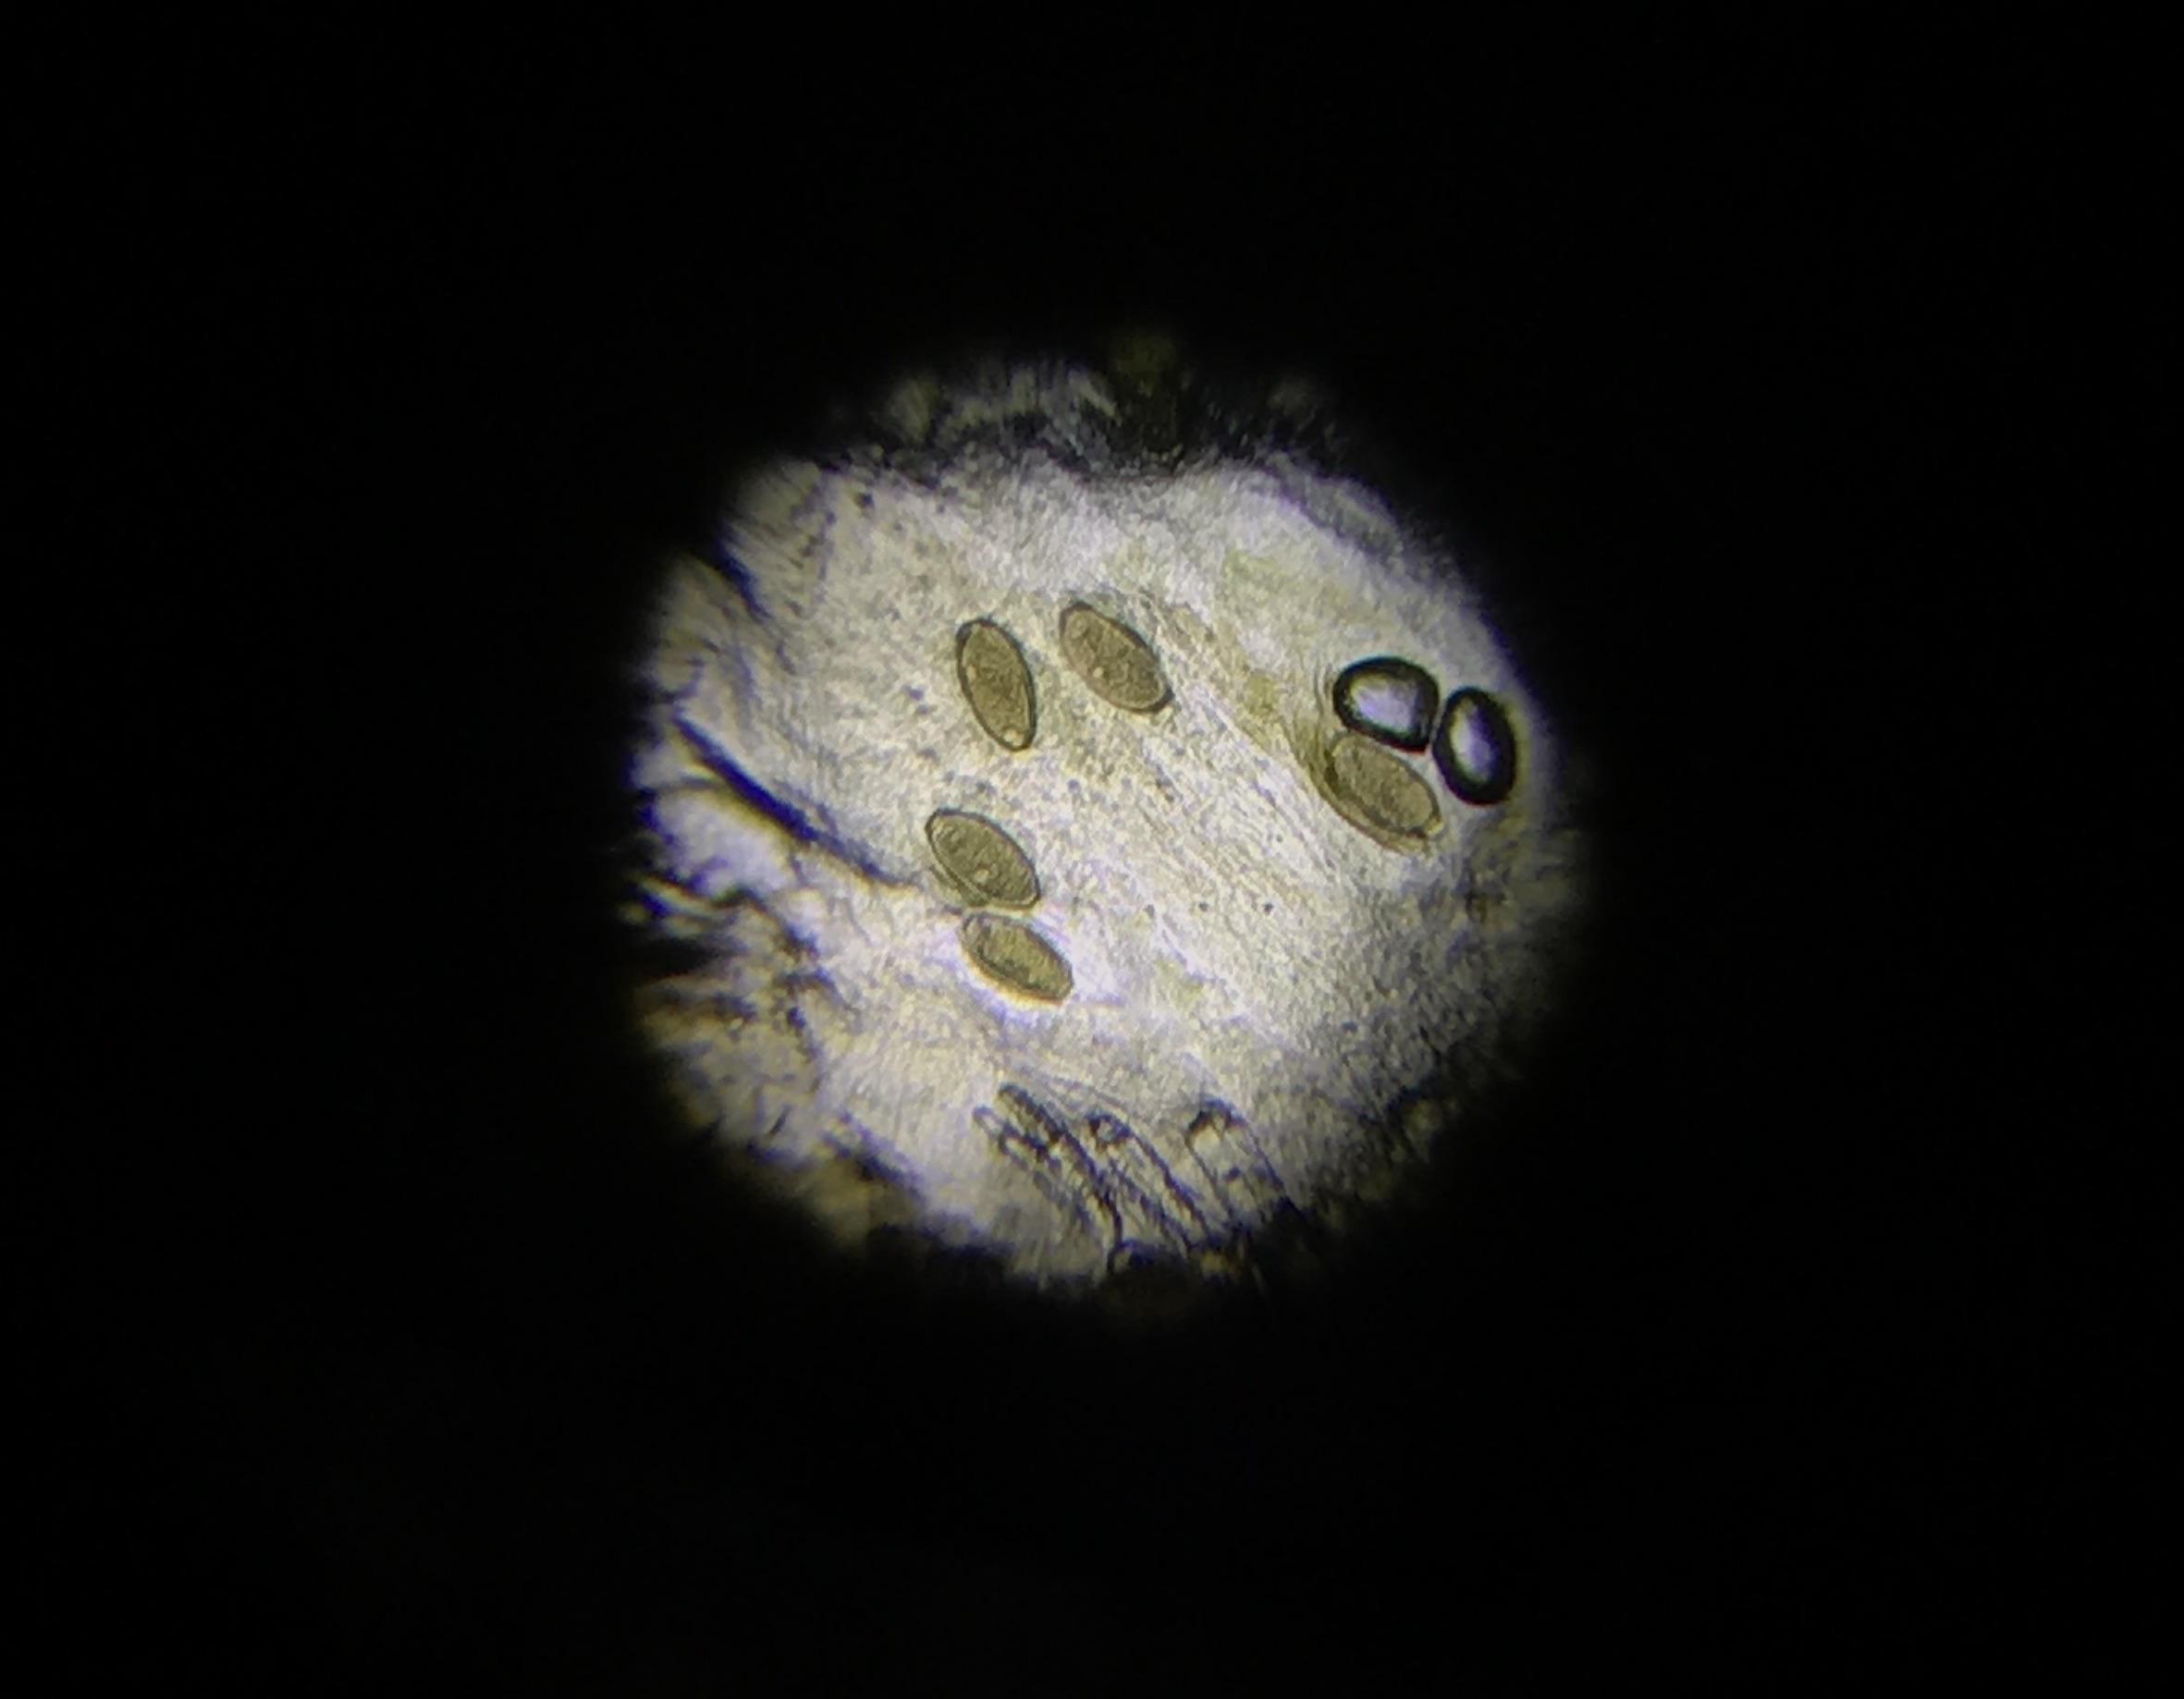

When hedgehogs come into our care, one of the first things that we do is test a fecal sample in order to find out what endoparasites the hedgehog is suffering from. Hedgehogs very often have some sort of parasite that is causing them issues, so it is important to get this tested, and treated, immediately. The image shows the eggs of ’roundworm’ (Capillaria spp.), which are the endoparasite most frequently found in hedgehog faeces.